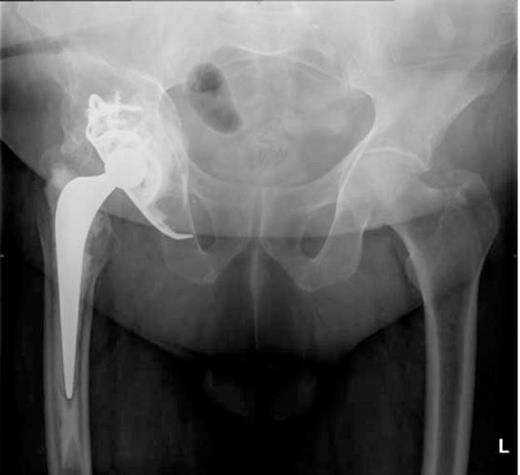

The acetabular screws were seen projecting medially into the pelvis with the anterior screw closely abutting the external iliac artery and vein causing compression (Figure 2).

A CT Scan of the pelvis showing compression of external iliac vein by acetabular screw